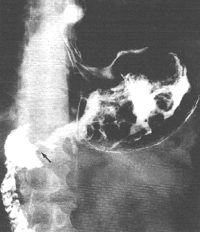

Case 33.10 S.F., 49 year old male. Radiology: 6.0 cm nodular and constricting pyloric filling defect. Smooth, concave indentation base of duodenal bulb (Fig. 33.10). Operation: Pyloric mass with serosal spread, adherent to pancreas. Lymph node metastases. Billroth II. Gastric histology: well differentiated adenocarcinoma. Duodenal histology: spread into serosa and muscularis of duodenum. Duodenal mucosa and Brunner's glands free of tumor cells.

![]() |

| Fig. 33.10.Case S.F. Nodular and constricting pyloric filling defect. Smooth, concave indentation base of duodenal bulb. |